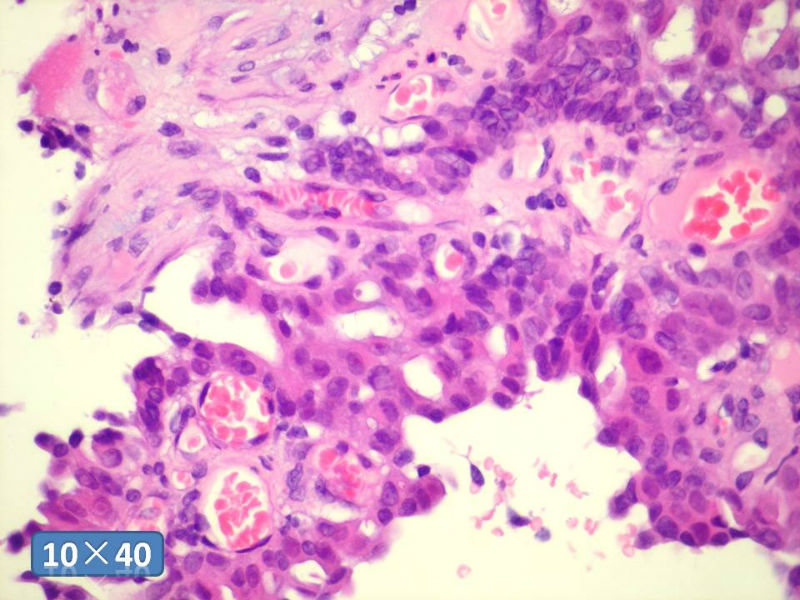

只能说是乳头状瘤

是不是导管内

乳头状瘤 and 导管内乳头状瘤 are the same; Benign lesion.

After you work up and you still cannot be sure it is benign , atypical or maignant lesion, you can call 乳头状lesion.

If this is excisonal case, you should figure out the nature of the papillary lesion.

我的意思就是提醒大家 在不是很确定的情况下 尽量少给自己套枷锁